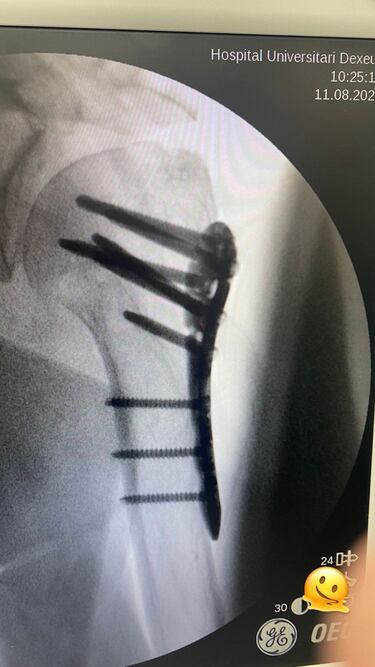

Milá comparte la radiografía de su hombro

Además, la televisiva ha querido compartir con sus más de 255.000 seguidores una imagen de la radiografía de su hombro izquierdo, donde se ha podido ver una gran placa de metal fijada con varios tornillos para poder sujetar en su lugar el hueso hasta que suelde.